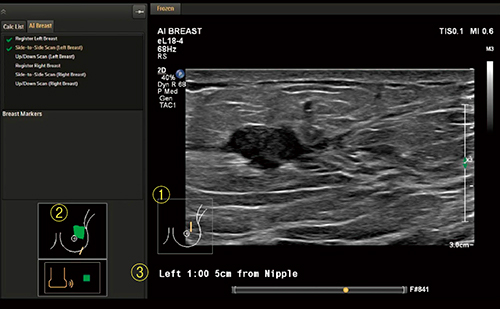

■乳房エコーの最新技術:AI Breast

“AI Breast”は,マットレスに内蔵された磁場発生装置でプローブの位置を自動検出し,画像データと一緒に保存する機能である(図3)。従来,手動で合わせる必要のあったプローブマークが追従するため,より正確なプローブ位置を自動で残すことができる。また,スキャンした軌跡が表示・保存されるので,データの客観性が向上し,スキャン技術の向上にもつながる。さらに,ワンボタンで病変の乳頭からの方向と距離を計測し表示することも可能であり,術前化学療法後の病巣部位の同定などに活躍が期待される。

図3 AI Breast機能

(1)プローブマークの自動追従,(2)走査軌跡のペイント,

(3)乳頭腫瘤間距離のワンボタン表示